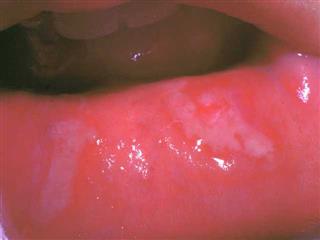

Avec ce médicament et ses proches, surtout CORROSIVUS, le chirurgien-dentiste se trouve en pays de connaissance. Ce sont sans doute les deux médicaments les plus souvent retrouvés dans les aphtoses buccales. Cela n’est pas suffisant pour les prescrire systématiquement. La pollution par le mercure est à l’ordre du jour et les amalgames ne sont pas les seuls responsables. Mais il s’agit là d’un autre problème.

La poussée aiguë d’aphtose buccale s’inscrit dans un contexte de gingivite ulcéreuse, avec une hypersalivation nauséabonde, des douleurs brûlantes aggravées par les boissons trop chaudes ou trop froides, une langue sale, flasque et étalée, gardant l’empreinte des dents. Le patient décrit un goût métallique prononcé. L’aggravation nocturne est de règle, la chaleur du lit est mal supportée, elle provoque des sueurs abondantes qui laissent le patient mal à l’aise. Dans ce contexte, il faut donner MERCURIUS SOLUBILIS 7 CH une fois par jour, plus un bain de bouche avec CALENDULA T.M. et PHYTOLACCA T.M. On peut préférer MERCURIUS CORROSIVUS si le tableau local est particulièrement grave : ulcérations plus profondes, douleurs brûlantes plus intenses.